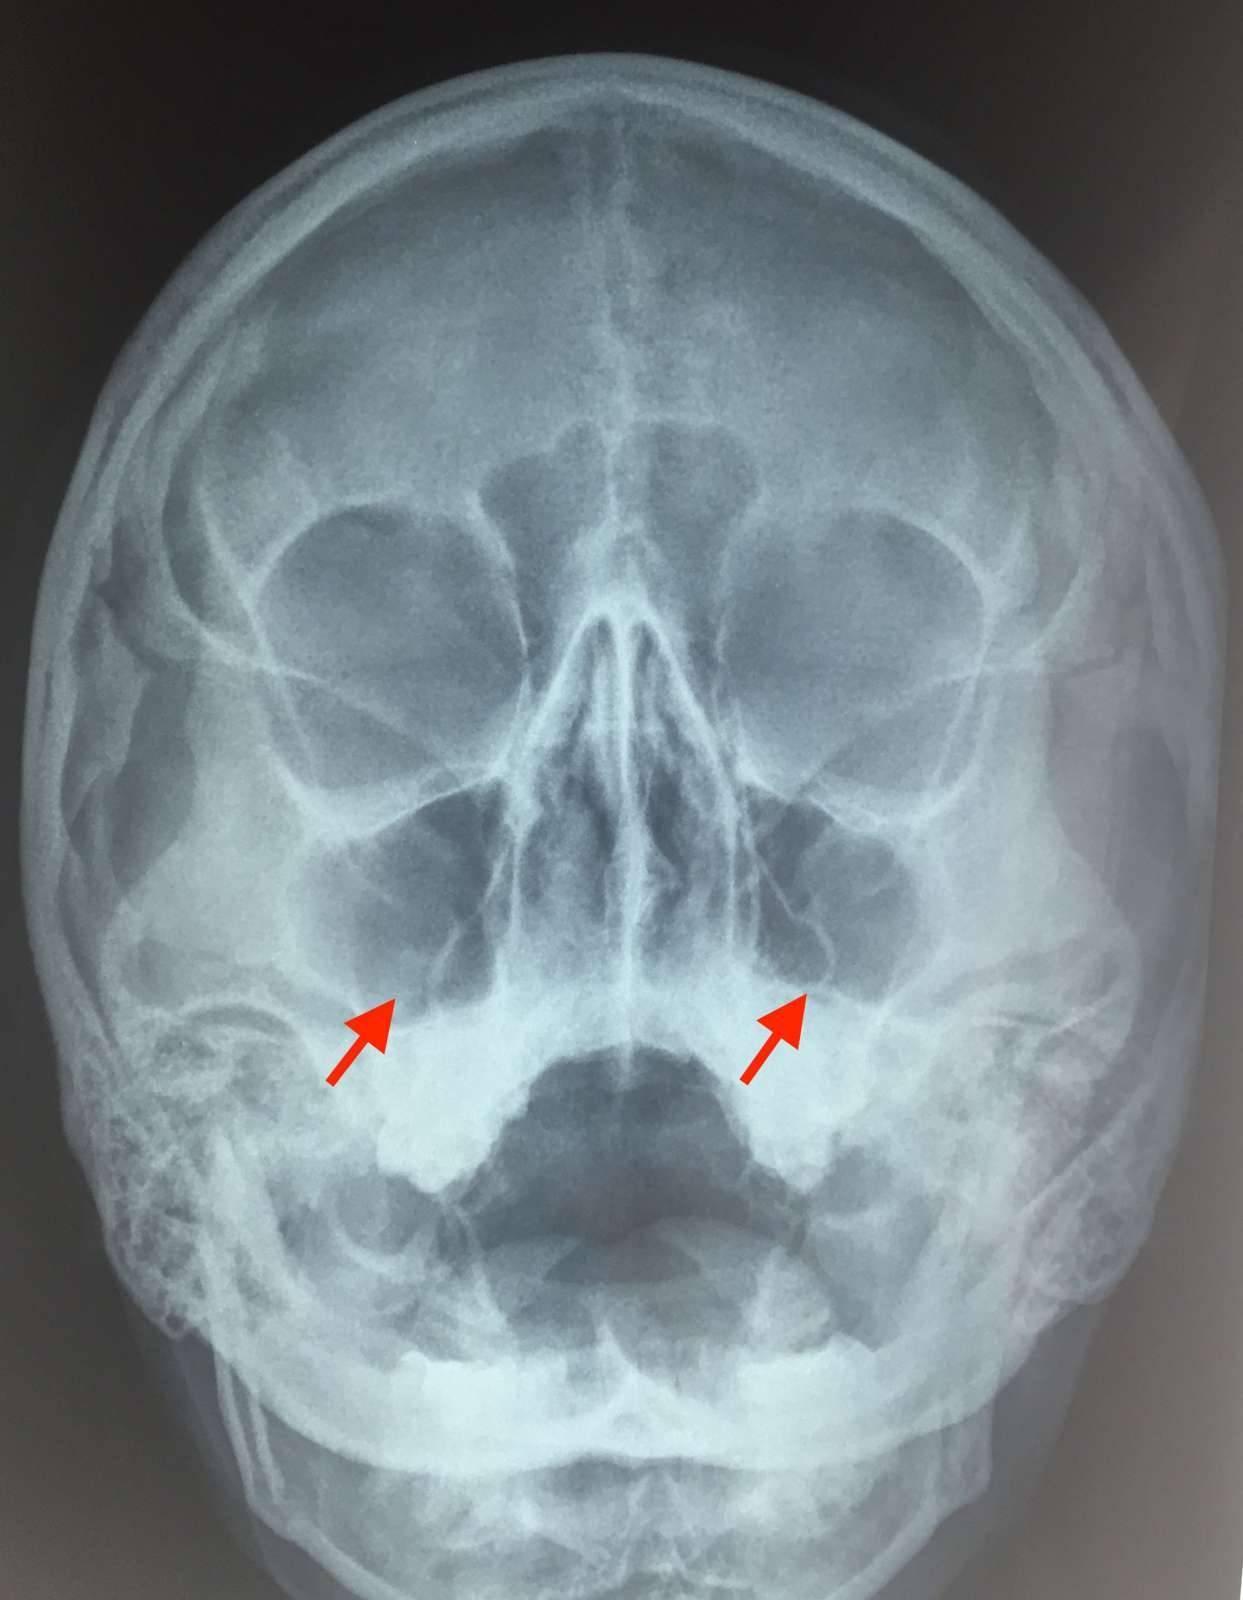

Если судить по месту локализации воспаления, гнойный гайморит бывает односторонним и двусторонним. При двустороннем гайморите воспалены обе пазухи, при одностороннем – либо правая, либо левая. Соответственно, и гайморит будет правосторонним или левосторонним.

Острая форма начинается и развивается стремительно и характеризуется яркими симптомами. Самый узнаваемый признак воспаления гайморовых пазух – сильная боль в переносице и месте локализации пазух – под глазами в области щёк. Гной, находящийся в пазухах, давит на их стенки, что вызывает болевые ощущения. Боль становится сильнее в вечерние часы и при наклоне головы. Иногда она может отдаваться в висках или челюсти.

Другой явный признак заболевания – гнойные выделения из носа зелёного или жёлтого цвета, которые могут иметь неприятный запах. В некоторых случаях наблюдается стойкая заложенность носа, когда соустья пазух перекрыты, и насморк отсутствует, так как гнойные массы не могут выйти наружу. Заложенность носа приводит к появлению гнусавости в голосе и снижению обоняния.

Гнойный гайморит: лечение и правильная диагностика

Количество чужеродных бактерий может оказаться огромным, тогда в ответ организм вырабатывает такое же огромное количество лейкоцитов (диагностируется таким симптомом, как лейкоцитоз). Повышенное СОЭ (скорость оседания эритроцитов) и значительно более высокий, чем обычно, уровень лейкоцитов в общем анализе крови покажут врачу состояние, так называемой, воспалённой крови.

Но бывает и так, что лейкоциты не в силах одолеть инфекцию и погибают. Образуется гной — скопление погибших лейкоцитов. Тогда это уже гнойный гайморит — лечение должно быть немедленным и правильным.

Когда слизисто-гнойные массы не могут выйти из гайморовых пазух, они начинают «бродить». Любой здравомыслящий человек поймет — пора в ЛОР клинику. С гнойным воспалением, разгорающимся рядом с головным мозгом лучше не шутить! Нужно обращаться к врачу, не дожидаясь перехода гайморита в хроническую форму и прочих опасных осложнений.